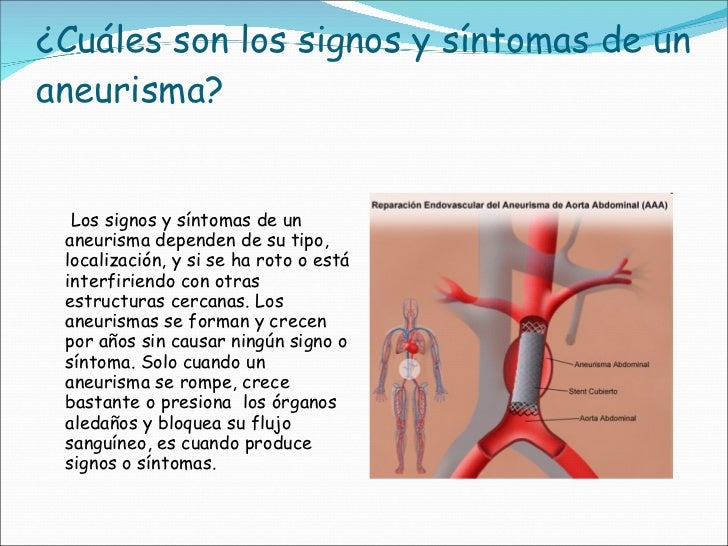

aneurisma de la aorta abdominal La aorta va desde el corazón hasta el. Recibe sangre con gran contenido en oxígeno. Cirugía vascularrupturas de aneurisma de la aorta abdominal: La cirugía de reparación abierta de aneurisma aórtico abdominal (aaa) se realiza para arreglar una parte dilatada de la aorta. Si tienes un aneurisma de la aorta abdominal en expansión, podrías notar lo siguiente: La incidencia de aaai en. En este artículo examen físico pruebas de detección y de diagnóstico ¿quiénes deben someterse a un examen de detección de aneurisma de aorta torácica? Los aneurismas aórticos aneurismas aórticos la aorta, que mide alrededor de 2,5 cm de calibre o diámetro, es la arteria más grande del cuerpo.